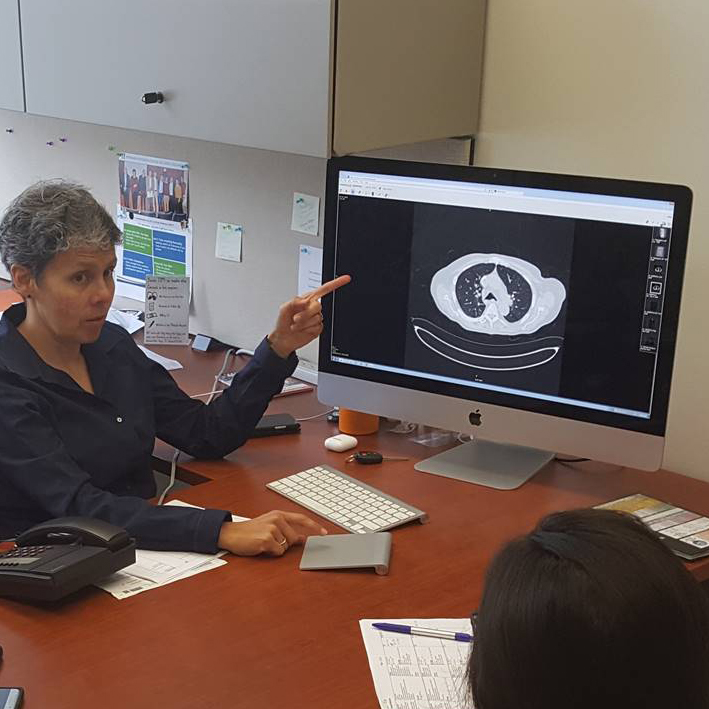

Abdominal Imaging →

The mission of the Abdominal Imaging Fellowship is to train well-rounded abdominal radiologists, scholars, educators and leaders who can provide outstanding care to advance the health and well-being of patients, contribute to advancing medical knowledge, and achieve their career goals in supportive and collegial environment.

Musculoskeletal Radiology →

The mission of the Musculoskeletal Radiology Fellowship Program at UMass Chan Medical School is to provide fellows with high-level, state-of-the-art training in musculoskeletal radiology, and to produce skilled and competent musculoskeletal radiologists who will succeed in both academic and private practices.

Neuroradiology →

The mission of the Neuroradiology Fellowship Program is to provide an in-depth, comprehensive neuroimaging experience, and expose fellows to research, quality assurance methods and leadership initiatives. Fellows train in a supportive, collegial, tertiary care hospital setting that enables them to provide outstanding health care, contribute to advancing medical knowledge and achieve their career goals.